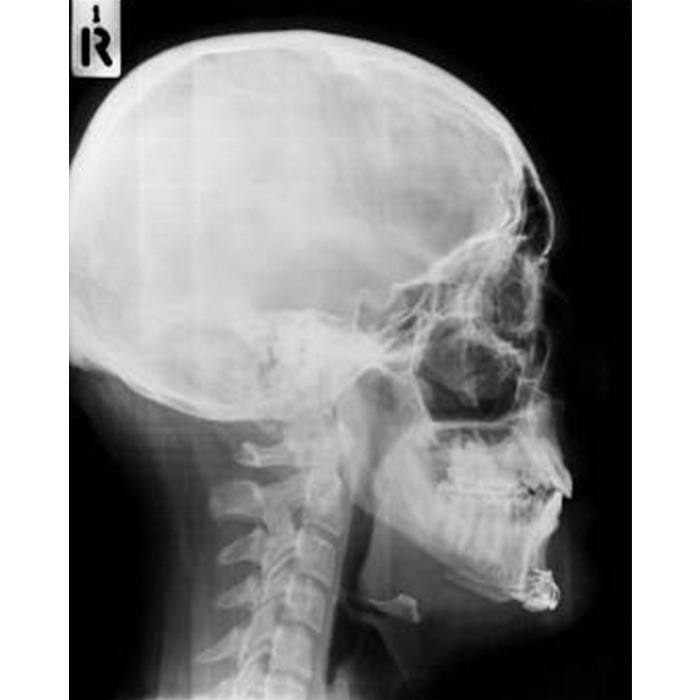

| Before | After |

The procedure for forehead contouring type 3 typically involves making an incision along the hairline. The surgeon will then remove a section of the forehead bone to reduce the size of the forehead. The remaining bone is then reshaped to create a more curved, rounded shape. In some cases, the surgeon may also use a technique called osteotomy, which involves cutting and repositioning the forehead bone to create a more feminine shape.

Once the reshaping is done, the skin is then repositioned over the new bone shape, the incision is closed and the patient is placed in a bandage or a surgical garment to protect the area. In some cases, the surgeon may also use a technique called hairline lowering, which involves moving the hairline forward to create a more feminine appearance.